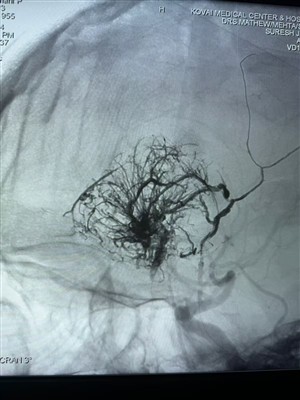

В Індії зареєстровано перший випадок гіперваскулярної пухлиниРаді поділитися цим першим випадком гіперваскулярної пухлини, проведеним в Індії. Його лікували системою Lava Liquid Embolic System від NeuroSafe Medical Co., Ltd. Завдяки доктору Метью Черіану. Ві...